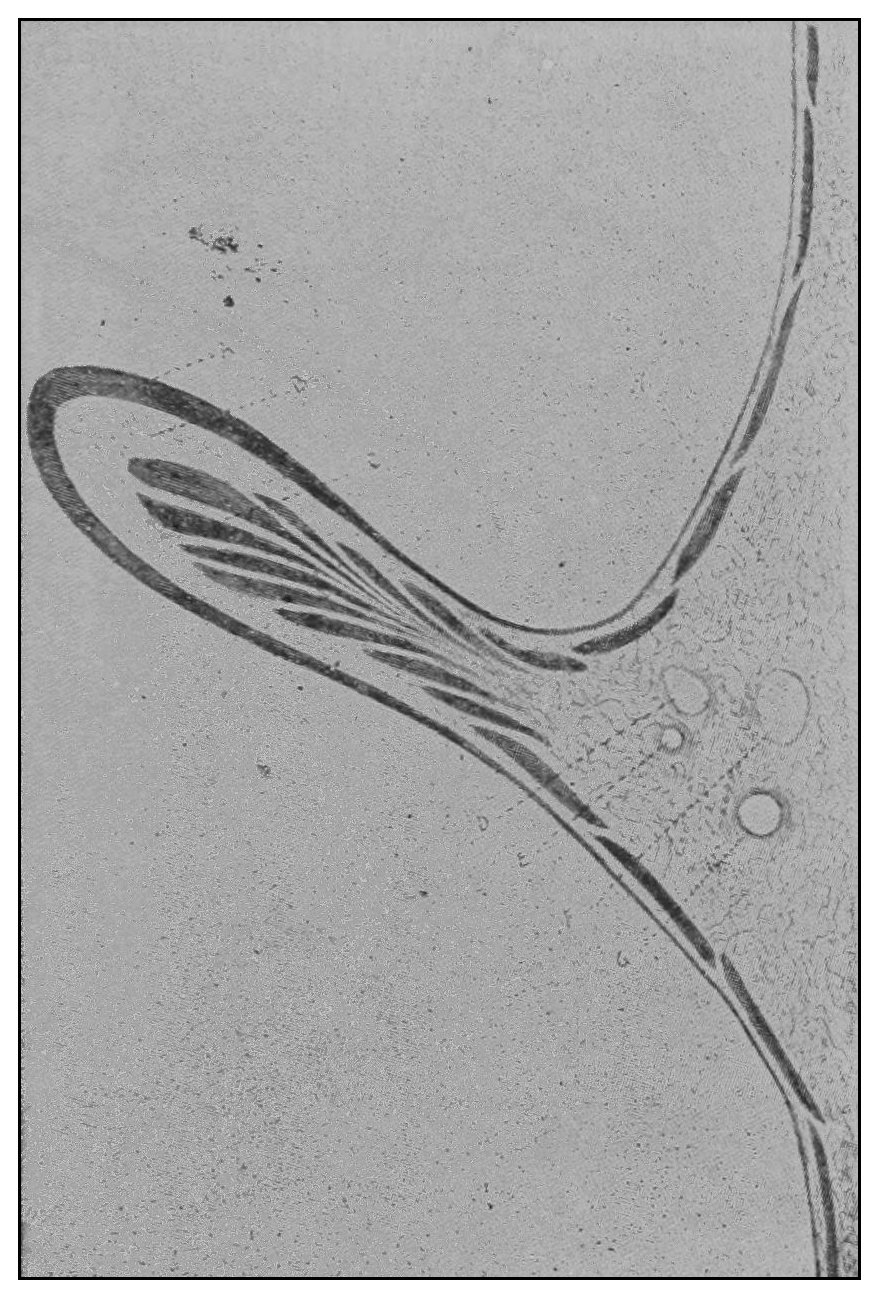

The photographic reproductions here published are documentary evidence of the existence of the obstructions under discussion. The sketch, Fig. 33, which was drawn from the valve while under the microscopic lens, exhibits the character of these obstructions and proves it that of a typic anatomic valve, and the absence of permanent bands of any other character in this organ is evidence that the semilunar valves and the so-called plica transversalis recti, Falten des Rectums, sphincter ani tertius, superior sphincter, and detrusor fecium muscles are one and the same thing and this thing is essentially a valve. It is most prominent when the gut is most distended.

(c) The operator should observe the degree of rectal distention, the situation and number of the rectal[49] valves, their propinquity to one another when passive, and the relation of one valve to another at the time of the patient’s bearing down. Under pressure of the proctoscope if possible, or the hook if necessary, each valve should be effaced or displaced, and in regular order each of the rectal chambers should be carefully inspected. A proctoscopic mirror may be necessary for viewing the supravalvular surfaces (Fig. 18). The examination being finished: